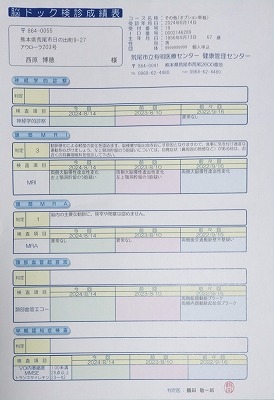

090 脳ドック

2024.18.14 荒尾市民病院 2023.08.10 荒尾市民病院

2024 PDF 2023 PDF

22.9.16 荒尾市民病院